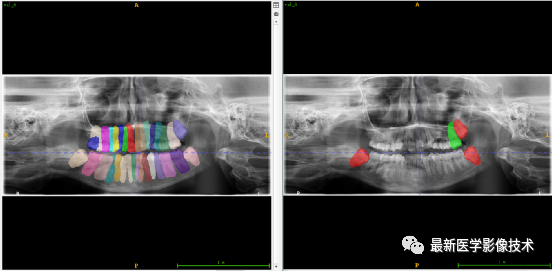

验证集牙齿分割计数和异常牙齿分割识别

左图是分割计数,右图是异常牙齿分割识别结果